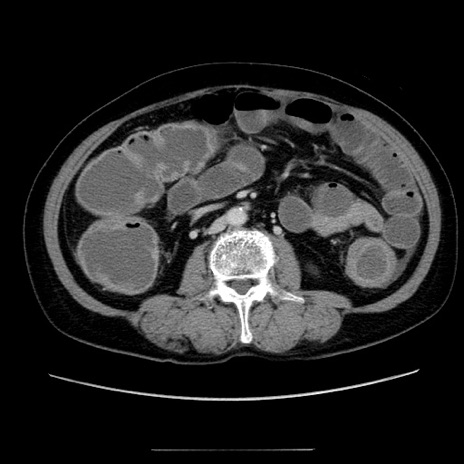

症例5(横断像)

【症例】70歳代女性

【主訴】お腹が張る

【現病歴】1週間くらい前から腹部膨満の自覚あり。昨日夜から増悪したため、本日救急外来受診。

【身体所見】意識清明、BT 36.5℃、BP 165/106mmHg、HR 80bpm、SpO2 98%、腹部:膨満、軟、自発痛・圧痛なし、触診にて不快感あり、腸蠕動音:減弱

【データ】WBC 12600、CRP 1.04